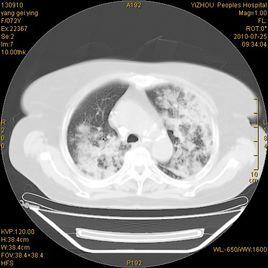

腦CT掃描是檢查可疑的急性ICH患者的首選方法。當單個腦葉出血出現在淺表部位並伴或不伴向蛛網膜下腔或腦室內局部擴展的皮質受累時,均提示為CAA相關性出血。也可能存在僅局限於腦葉區域的多發性出血的證據。

最為常見的出血部位為累及皮質和皮質下白質的額葉和頂葉出血。有時可同時累及數個腦葉。深部中央灰質核、胼胝體和小腦有時也可受累。CAA引起殼核、丘腦或腦幹出血者罕見。

單純性蛛網膜下腔、腦室內和硬膜下出血雖可見到,但很罕見。除非有其他病因,尤其是動脈瘤存在,CAA不會引起孤立性的蛛網膜下腔出血。

CAA相關性痴呆患者的CT掃描可見到類似於Binswanger病的白質腦病,還可發現腦萎縮,特別是那些有認知功能障礙和出血史的患者。

MRI可顯示多發性皮質和皮質下大的或小的淤點狀出血灶,患者如無出血史,則提示曾經發生過無症狀出血。MRI梯度回波(GRE)序列可顯示鐵沉積的證據,後者為陳舊性出血的表現。對於腦葉出血者,陳舊性淤點狀出血的證據有助於CAA的診斷。GRE-MRI還可用於監測疾病的進展、評估將來的危險性以及評價治療干預的效果。在基線水平時,GRE-MRI上發現的陳舊性ICH病灶越多,將來發生ICH、認知功能障礙、生活不能自理和死亡的危險性就越大。對於合併血管炎的患者,MRI可見到腦脊膜增厚。